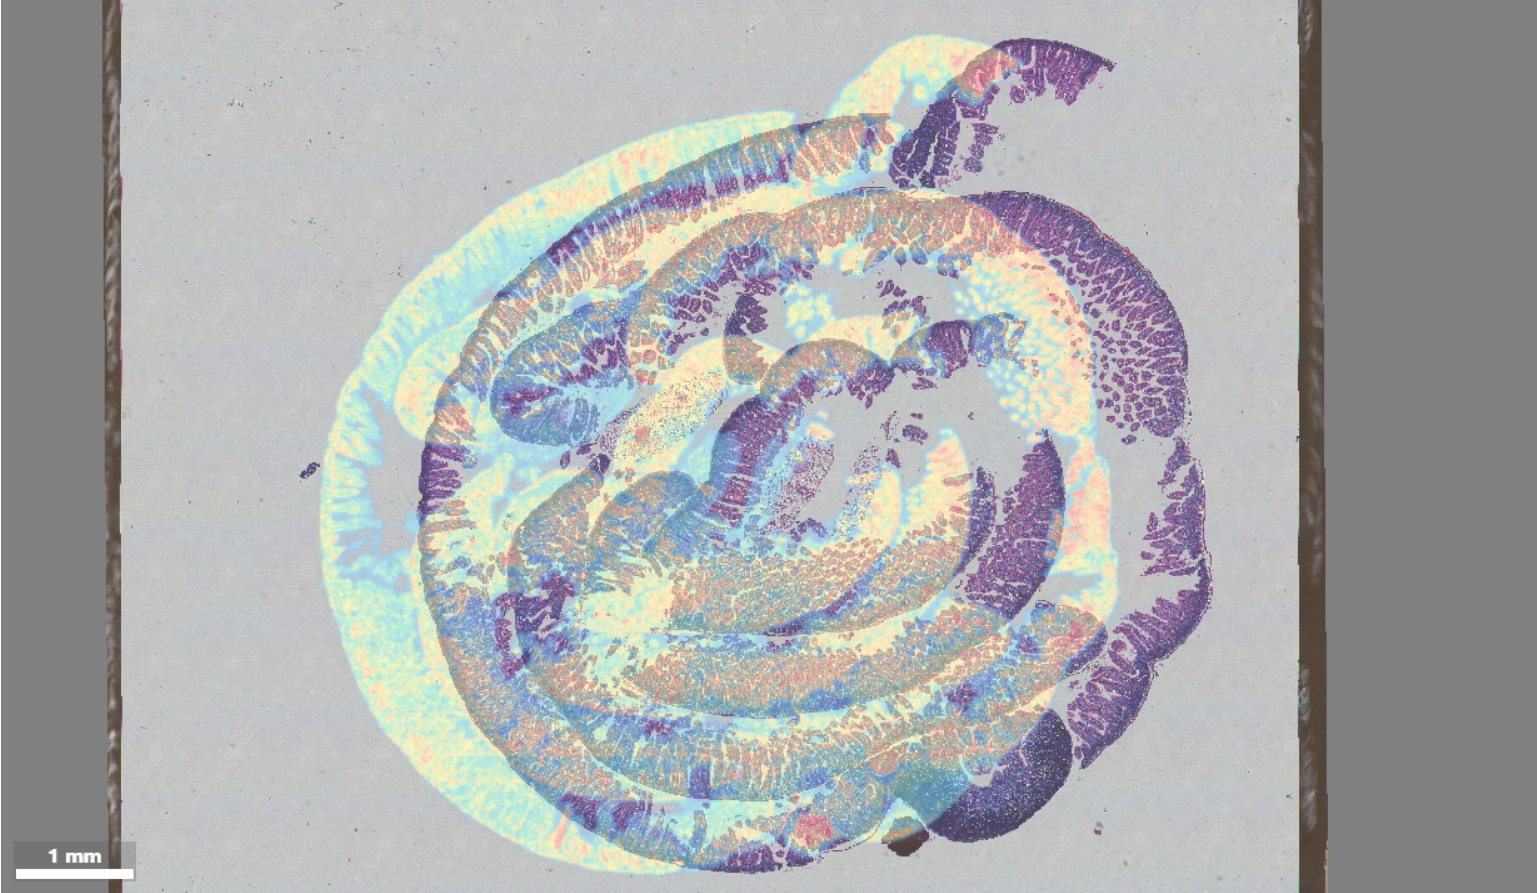

A matrix heatmap and an H&E-stained image for registration

Tissue segmentation on an H&E-stained image